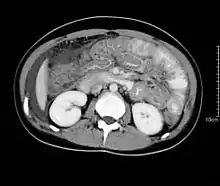

وقد توضح الأشعة المقطعية تثخن عقدي شاذ في أقصي المعدة والأمعاء الدقيقة البعيدة، ولكن يمكن أن توجد هذه النتائج أيضاً في حالات أخرى مثل مرض كرون والأورام اللمفاوية.